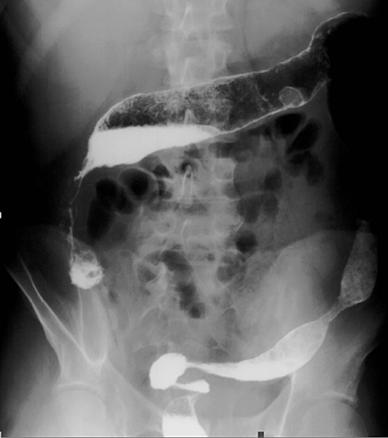

Sténose compliquant l'évolution d'une maladie de Crohn et correspondant à un adénocarcinome colique après analyse histologique de la pièce opératoire.